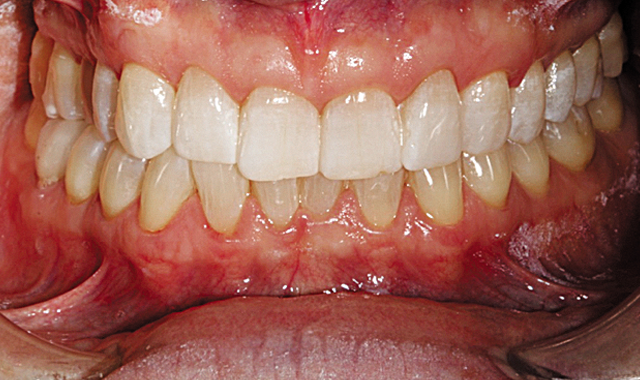

Our Invisalign treatment led to a very successful clinical result. The crowding and the asymmetries of tooth position, arch form and gingival levels were beautifully corrected (Figs. 14-16).

Fig. 14

Fig. 15

Fig. 16